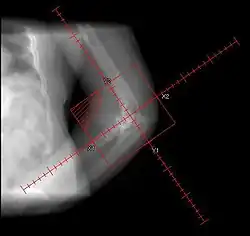

During the early stage, an x-ray will not be helpful because there is no calcium in the matrix. (In an acute episode which is not treated, it will be 3– 4 weeks after onset before the x-ray is positive.) Early laboratory tests are not very helpful. Alkaline phosphatase will be elevated at some point, but initially may be only slightly elevated, rising later to a high value for a short time. Unless weekly tests are done, this peak value may not be detected. It is not useful in patients who have had fractures or spine fusion recently, as they will cause elevations.

The only definitive diagnostic test in the early acute stage is a bone scan, which will show heterotopic ossification 7 – 10 days earlier than an x-ray. The three-phase bone scan may be the most sensitive method of detecting early heterotopic bone formation. However, an abnormality detected in the early phase may not progress to the formation of heterotopic bone. Another finding, often misinterpreted as early heterotopic bone formation, is an increased (early) uptake around the knees or the ankles in a patient with a very recent spinal cord injury. It is not clear exactly what this means, because these patients do not develop heterotopic bone formation. It has been hypothesized that this may be related to the autonomic nervous system and its control over circulation.[3]

Prophylactic radiation therapy for the prevention of heterotopic ossification has been employed since the 1970s. A variety of doses and techniques have been used. Generally, radiation therapy should be delivered as close as practical to the time of surgery. A dose of 7-8 Gray in a single fraction within 24–48 hours of surgery has been used successfully. Treatment volumes include the peri-articular region, and can be used for hip, knee, elbow, shoulder, jaw or in patients after spinal cord trauma.